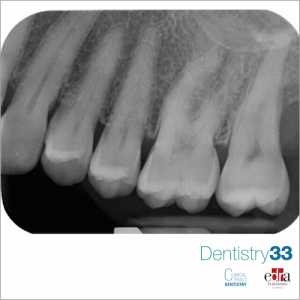

Authors: Prof Dr Daniele Cardaropoli, Dr Alessandro Roffredo

First of 3 clinical cases in which three-dimensional radiology has allowed us to avoid making diagnostic errors otherwise not evaluable with two-dimensional radiography alone.